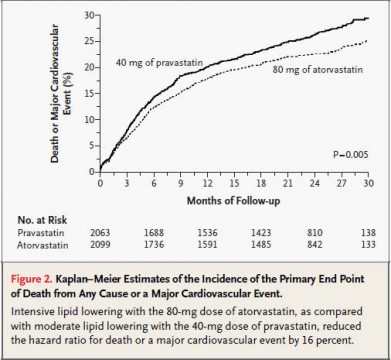

2004年4月8日

急性冠脉综合征患者接受阿伐他汀的治疗可以显著降低低密度脂蛋白(LDL)胆固醇、减少心血管病风险和提高生存率。此后,阿伐他汀成为了这种类型患者的标准辅助治疗,而不管他们的基础LDL水平如何。